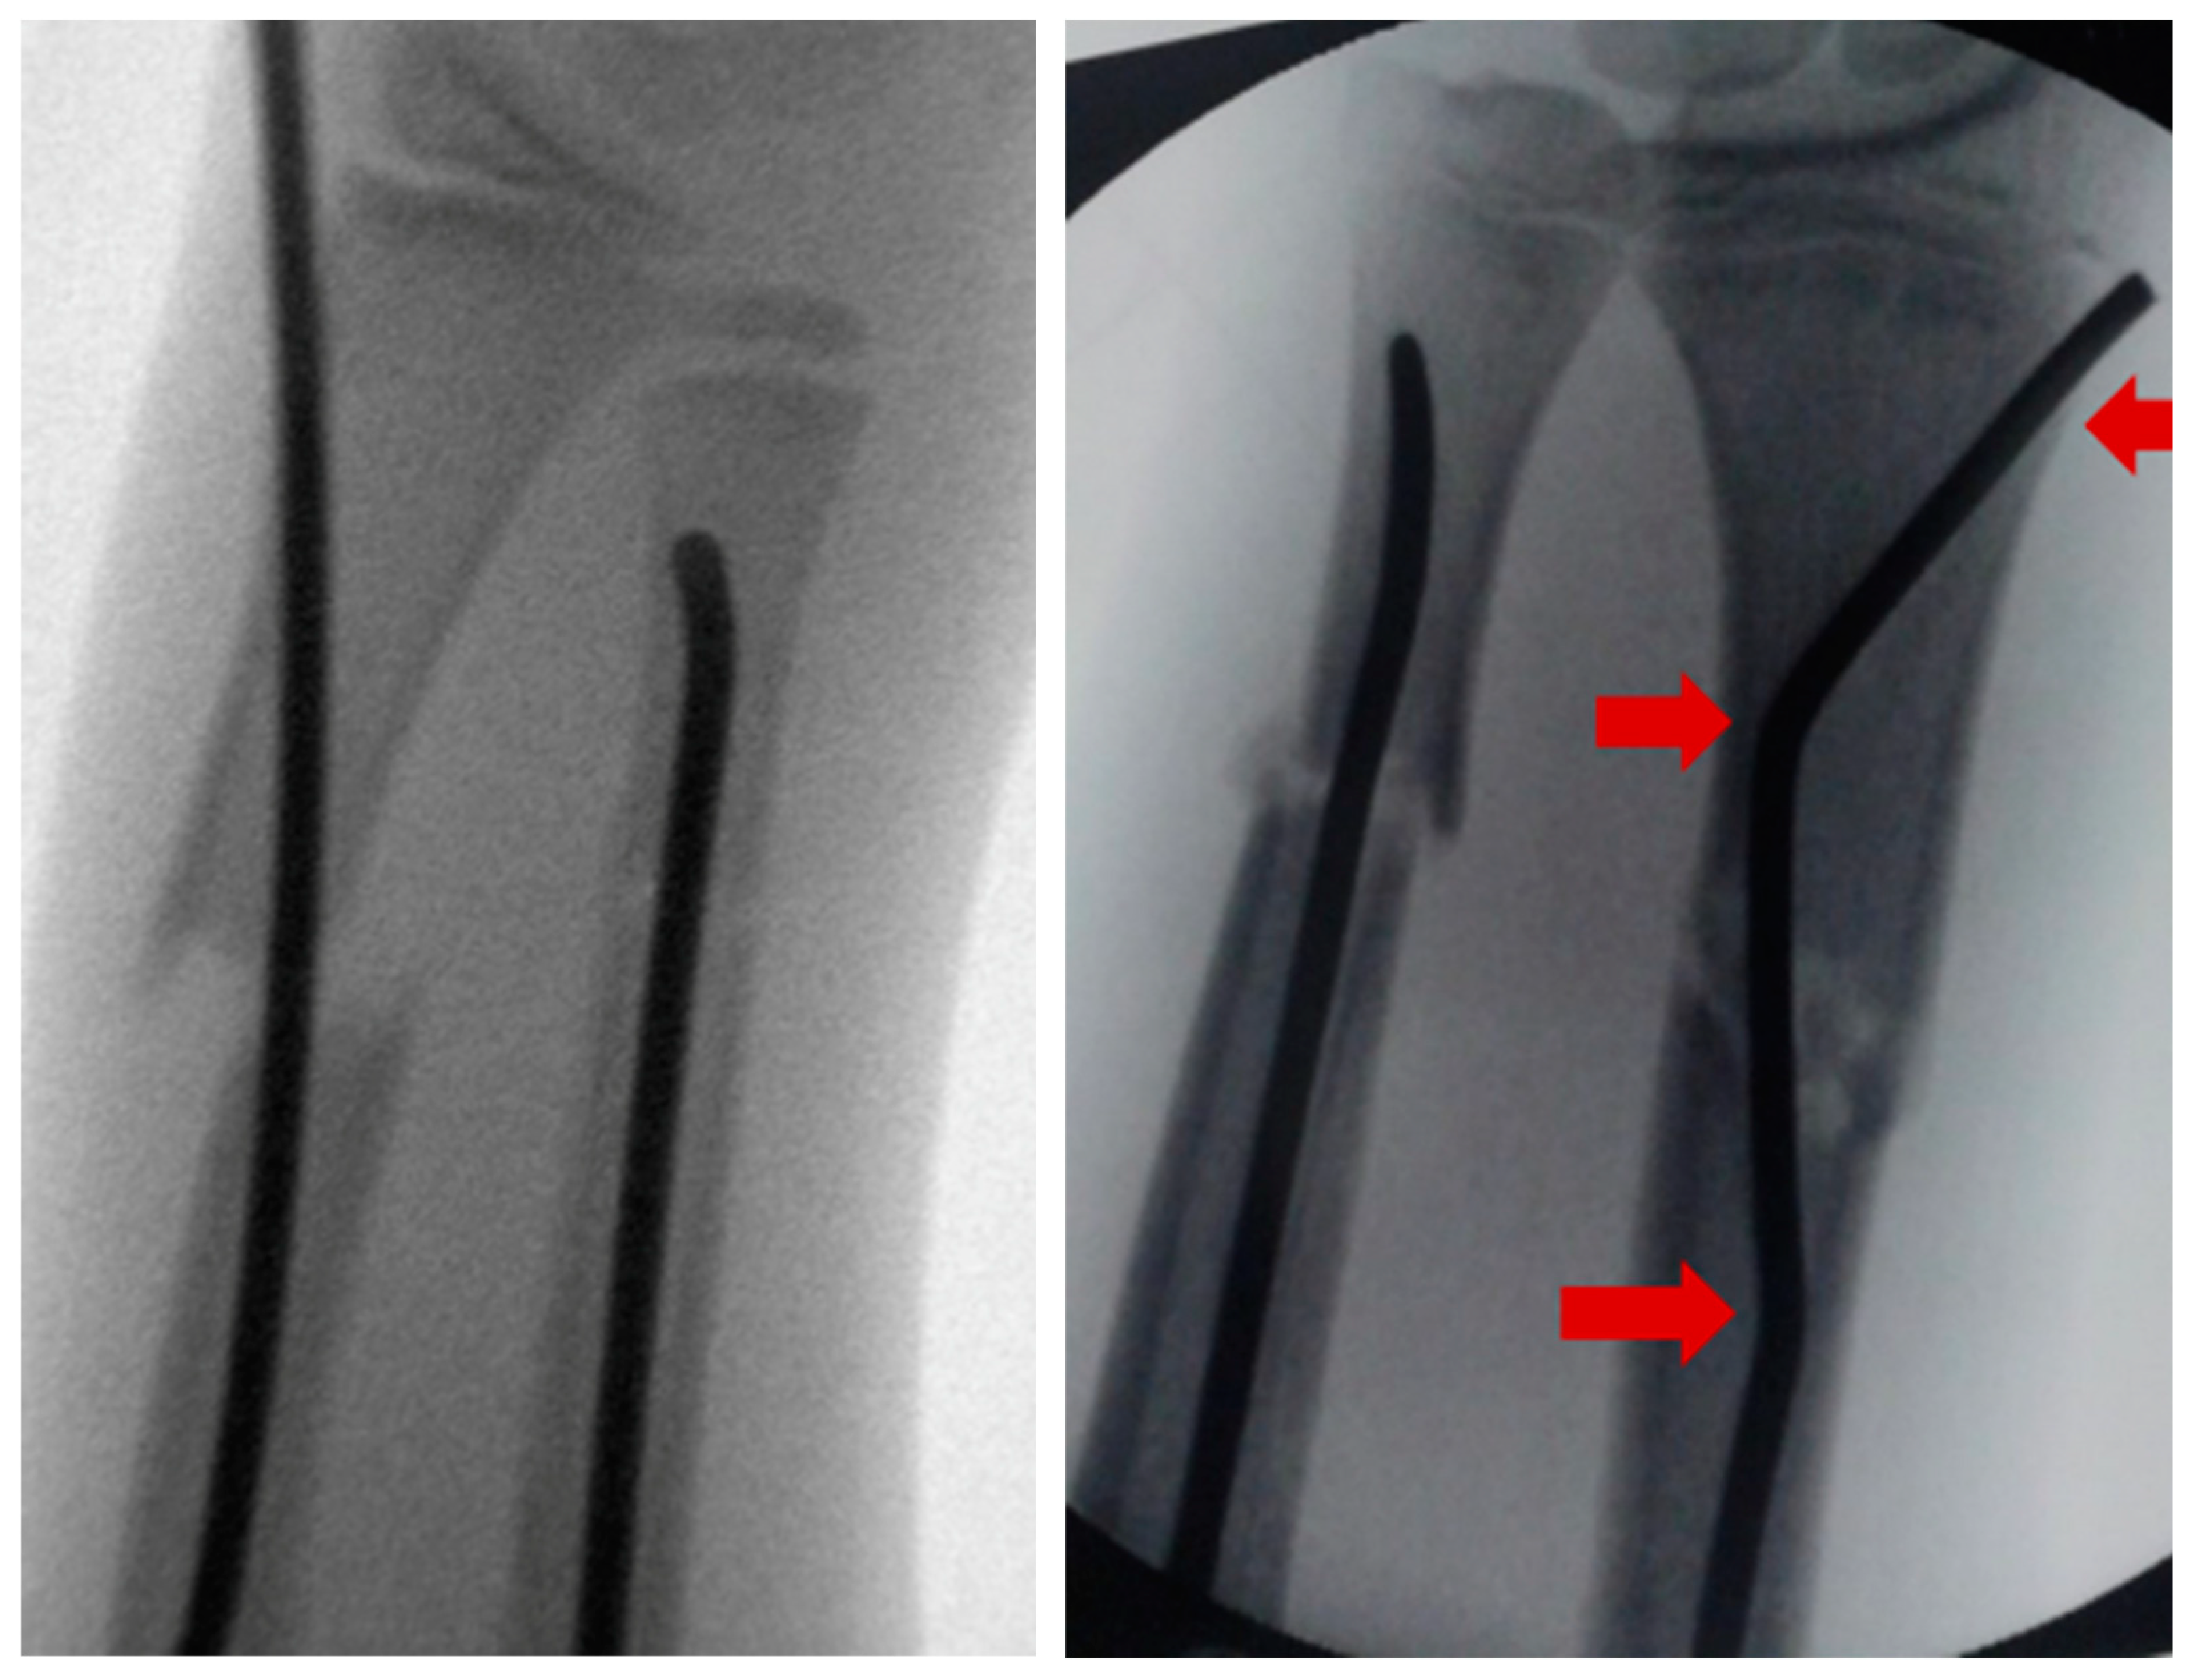

Intramedullary nails, however, if not pre-bent, usually lead to an unacceptable radial displacement of the distal fragment, which makes the situation sometimes worse than it was before (Figure 1). Pre-bending techniques have been described with a single kink, which is placed distal to the fracture, but these remain controversial due to lack of stability [3,10,11]. The same applies to unconventional techniques, such as locked wires [12].

The idea that this new surgical technique is based on is that, if a normal intramedullary nail being brought into the radius from the radial side of the distal radius, displaces the distal fragment radially, the solution would be to insert the nail from the ulnar side, which, however, is not possible, because this area cannot be accessed due to the close anatomical neighborship of the distal ulna. This makes it necessary to simulate an ulnar access. Therefore, the proximal (first) kink of the nail, which at the end of the procedure is placed proximal to the fracture, will push the radial corticalis of the proximal fragment radially, whereas the second kink (which can also be performed as a bend, see Scheme 1) pushes the distal fragment into an anatomical position and makes it possible for the nail to be brought into the distal radius using the established approach. If the entry into the bone is performed exactly with the diameter of the nail, stable osteosynthesis with three-point support is achieved (Figure 1).

Figure 1. Intramedullary nailing without pre-bending of the radial nail leading to a radial displacement of the distal fragment whereas double pre-bent nail ensures three-point support.